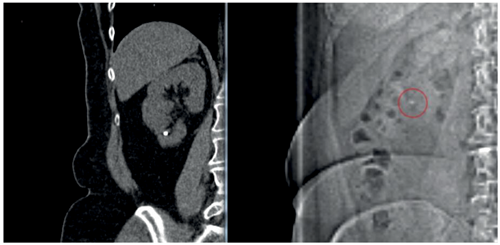

‘Percussion, diuresis and inversion’ (PDI), may be suggested to aid the passage of the lower pole stone fragments. In the Donaldson study [13], RIRS had a greater likelihood of achieving stone-free over SWL (risk ratio 1.31; 95% CI, 1.08-1.59), but this can be reduced with auxiliary manoeuvres such as PDI therapy [25].

Stone-free rates are suggested to range from 40-60% [26], depending on the methods used. Diuresis can be stimulated by a 500ml bolus of water or 20mg of furosemide, whilst inversion (of 45 degrees) and percussion are usually performed in the comfort of the patient’s home surroundings (Figure 3). Not surprisingly, this cannot always be feasible and therefore a suggested modified approach includes swimming after ingestion of 500ml of water.